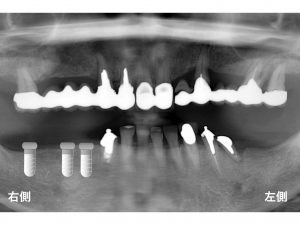

以下が15年前の初診時のレントゲンです。

下顎の左右の奥歯が欠損しており、

噛めない状態でした。

下顎左側の奥歯がグラグラしており、

痛いとのことでした。

この歯は、グラグラで、保存できる状態ではないため、抜歯と診断しました。

以下が下顎左右にインプラントを埋入した直後です。

そして、インプラントと骨がしっかりと結合するまで約2ヶ月待ち

被せ物を装着しました。

これが約15年前です。

以下の赤丸が神経のない歯です。

上顎の右側も

上顎の左側も

神経のない歯でブリッジを行っています。

以下が初診から15年後の現在の状態です。